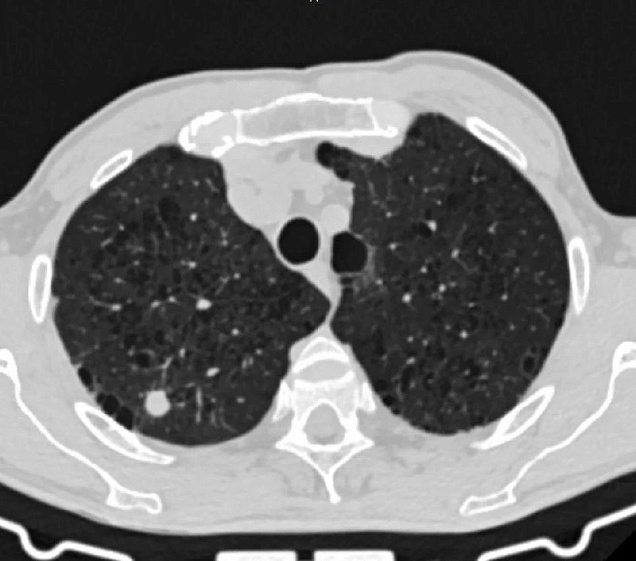

Чтобы уточнить диагноз, пациенту провели необходимые исследования, включая компьютерную томографию лёгких, бронхоскопию и современный тест на туберкулёз — ТиграТест. По итогам обследования медики приняли решение о хирургическом удалении небольшого участка лёгкого.

По результатам гистологического исследования мужчине был поставлен диагноз «туберкулез лёгких». Ему назначили лечение, пояснили в Министерстве здравоохранения Алтайского края.